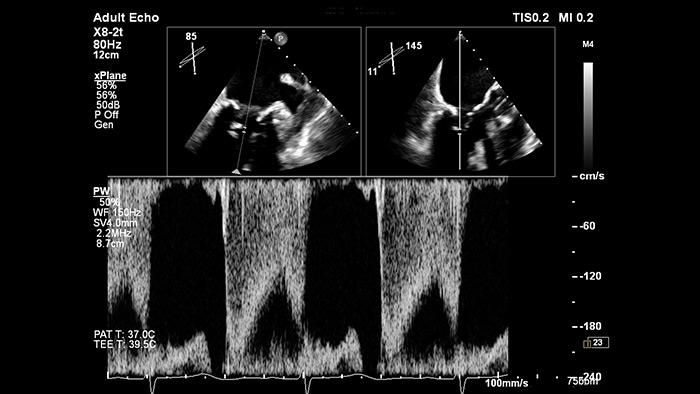

Gain confidence of correct gate placement when assessing cardiac flow with xPlane Doppler